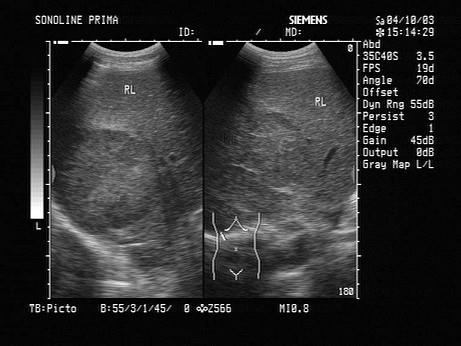

女,51岁,乏力,右上腹痛半个月。结合超声声像图,诊断为?(?)A.肝癌B.局限性脂肪肝C.肝包虫病D.肝囊肿E.肝脓肿

选项 A.肝癌 B.局限性脂肪肝 C.肝包虫病 D.肝囊肿 E.肝脓肿

答案 A